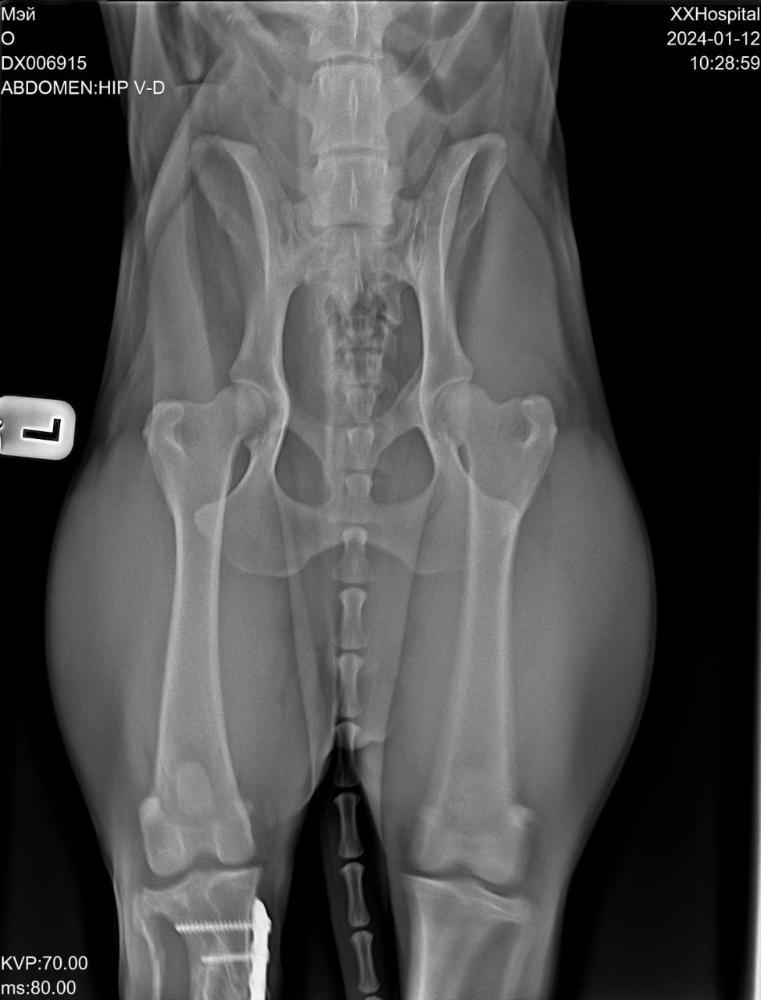

Светлана 2101 Опубликовано 12 января, 2024 Опубликовано 12 января, 2024 Сегодня съездили с Мэем к ортопеду. Сделали рентген. Сразу скажу, я осталась очень довольна приемом, содержательной беседой с врачом. Но есть новости хорошие и не очень. Сделано - рентген грудной и поясничный отдел, тазобедренных суставов и рентген оперированной лапы. По позвоночнику - в прекрасном состоянии, нет признаков травмы и дегенеративных изменений, кроме единичного незначимого очага дискоспондилита в среднем грудном отделе. На одном позвонке только есть изменения ( на снимке красным). Это ни о чем .Никак на жизнь не влияет. Тазобедренные суставы в отличном состоянии, без признаков дисплазии. В оперированной лапе - конструкция стабильна, признаки консолидации отломков. То есть всё хорошо. Доктор сказал, что далее ещё больше укрепляться будет. Процесс нарастания костной мозоли ещё идёт. Новости не очень. Измерил угол наклона плато, это крепление связок. Не очень владею всеми терминами, но своими словами напишу, как поняла. Этот угол у Мэя 20°, норма 14, при значении 25 и выше сто процентов разрыв ПКС неминуем. Хоть доктор и написал в заключении, что риск разрыва ПКС невелик, но на словах мне сказал, что вероятнее всего рано или поздно связки порвутся. 20° это уже большое натяжение, рвутся и при 22-23. Соответственно, рекомендации режим спокойных прогулок в монорежиме без кучных игр для минимизации нагрузки на коленные суставы . То есть спокойный режим даже не столько для оперированной лапы, сколько угроза разрыва ПКС. По словам доктора, это генетическая предрасположенность. В беседе он так сказал, что, да вы можете стараться его ограничивать от прыжков, но один раз он не прыгнет, а в другой раз всё равно прыгнет. Теперь вы знаете, что можно ожидать, но совсем собаку не ограничить во всем. А Мэй как раз очень прыгучий. Он даже на подзыв не просто подбегает, а прыгает.И бежит он прыжками. Один плюс, что он не знает диванов, и нет этого туда-сюда по 20 раз в день. Но на улице он хочет бегать. И бегает он очень мощно.Теперь понятно, что надо помнить об этом и стараться минимизировать прыжки . Но до сих пор связки целы, а прожил он с ними уже несколько лет, и режим у него был наверняка активный, никто его не ограничивал. Есть надежда, что продержатся они и ещё. И опять здесь очень хорошо, что он на НП, натуральные коллагены и Хондроитины помогут укреплению связок и сохранят суставы и позвоночник ,которые сейчас в прекрасном состоянии . Вот такое обследование. Я очень рада, что нет проблем в позвоночнике и суставах. Но не без ложки дегтя. Всё равно спокойный режим прогулок и жизни. А там как сложится. Просто теперь мы об этом знаем, что можно ожидать . 4 3

Светлана 2101 Опубликовано 12 января, 2024 Опубликовано 12 января, 2024 Рентген грудного отдела, вот единственный позвонок с дискоспондилитом, остальные все красивые Рентген пояснично крестцового отдела. Без изменений. Рентген тазобедренные. Рентген конструкции на оперированной лапе и углы. 5